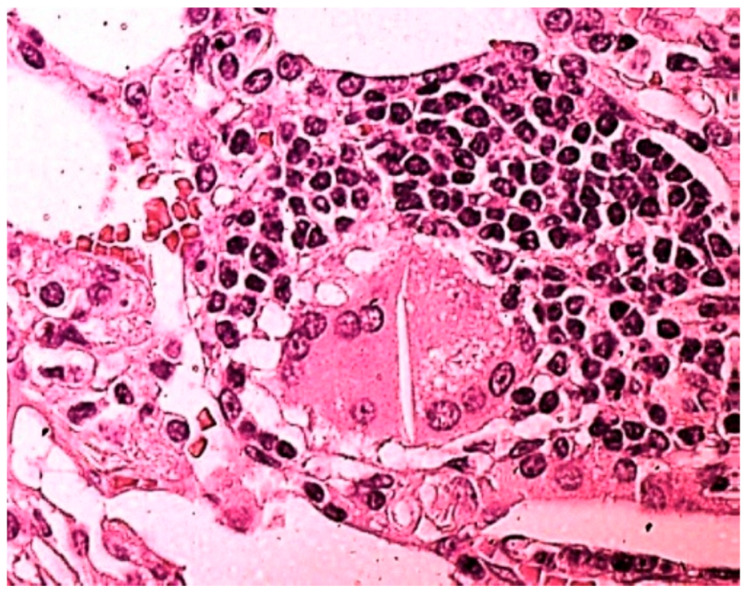

The patient in Figure 2, not included in Table 3 because at that time we had not developed yet the technique of searching for drugs in BAL [ref. 10] and lung tissue [ref. 11], smoked 20 tobacco cigarettes a day for 20 years; he had been snorting cocaine once a day for 10 years until the day before surgery; urine toxicological examination resulted positive for cocaine. Chest CT showed thickening of the peribronchovascular and septal interstitium, right apical thickening, diffuse micronodulia, and mediastinal lymphadenopathy. In BAL, there were CD4 lymphocytic alveolitis, increased neutrophil and eosinophil counts, numerous giant cells, mast cells, and birefringent bodies. The histological examination of the lung tissue showed interstitial fibrosis, granulomatous giant cell foci characterized by epithelioid cells, Langhans-type giant cells with cytoplasmic inclusions, attributable to asteroid bodies, and absence of caseous necrosis. The evaluation of the slide under a polarized light microscope highlighted the birefringence of needle-like inclusions (Figure 2), thin and elongated crystals between 10 and 40 microns in size, and with a morphology of organic fibers, such as cellulose, thus suggesting the diagnosis of pulmonary fibrosis and granulomatosis from cellulose-cut cocaine.

Desquamative interstitial pneumonia (DIP) is reported in users of large quantities of marijuana [ref. 20,ref. 21]. In our study, DIP-like reaction (Table 3) was found in 5/10 (50%) patients with cannabinoid-positive lung tissue and in 1/5 (20%) with cannabinoid-negative lung tissue. We observed the accumulation of macrophages in the five cannabinoid-positive patients with DIP-like reaction; absence in the only cannabinoid-negative patient with DIP-like reaction (patient n. 14, Table 3). Our finding suggests the responsibility of cannabis in causing DIP, especially taking into consideration the young age of the patients (24–27 years) (Table 3). Indeed, in DIP from other causes, the average age of onset of symptoms is between 40 and 60 years [ref. 22,ref. 23]. Not only can drugs be responsible, but also additives, adulterants, and cutting substances, such as cellulose, talc, and starch [ref. 2,ref. 6,ref. 24], as in the patient in Figure 2: the research in the granuloma was crucial for a correct etiological diagnosis.